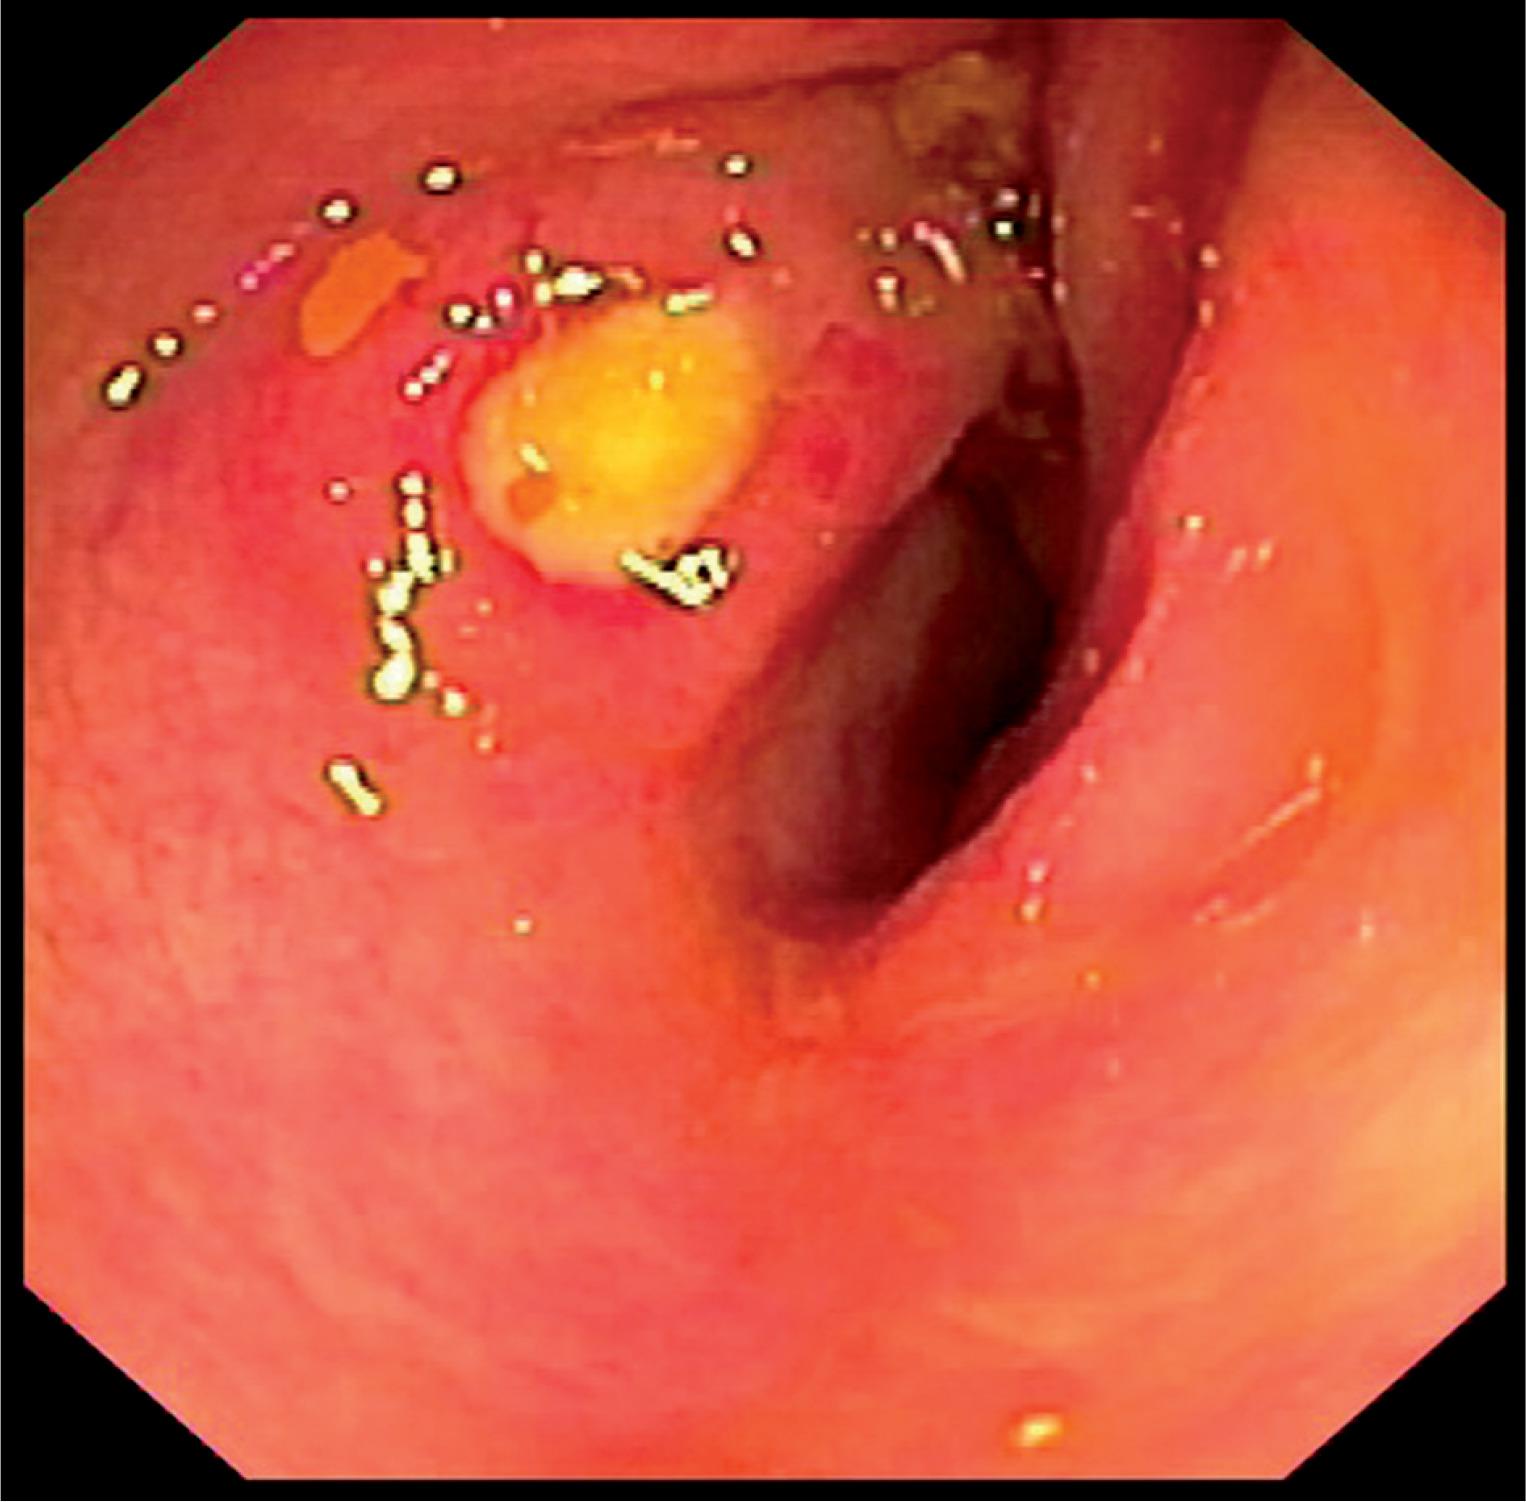

At day +35 she complained of acute abdominal pain accompanied by significant elevation of gamma glutamyl transpeptidase (3673 U/l), alkaline phosphatase activity (643 U/l) and a total and conjugated bilirubin level (5.17 mg/dl and 4.15 mg/dl, respectively). On magnetic resonance (MRI) cholangiopancreatography, the common bile duct (CBD) was widened with a diameter of 6 mm and in the distal part of CBD there were bile deposits of 5 × 3 mm size. She was qualified to urgent endoscopic retrograde cholangiopancreatography (ERCP). After sphincterotomy, removal of bile deposits was carried on with endoscopic basket. Additionally a 5 cm 7F prosthesis was inserted into the distal CBD (Fig. 2).

Fig. 2

ERCP showing a common bile duct (day +35): A) mildly dilated duct with biliary stone (black arrow) before extraction, B) with no signs of dilation after stone extraction (6 weeks later)